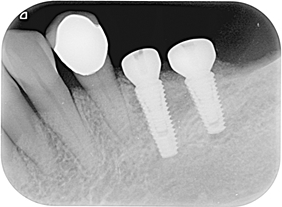

分別植牙後X光片

植牙後癒合狀況良好